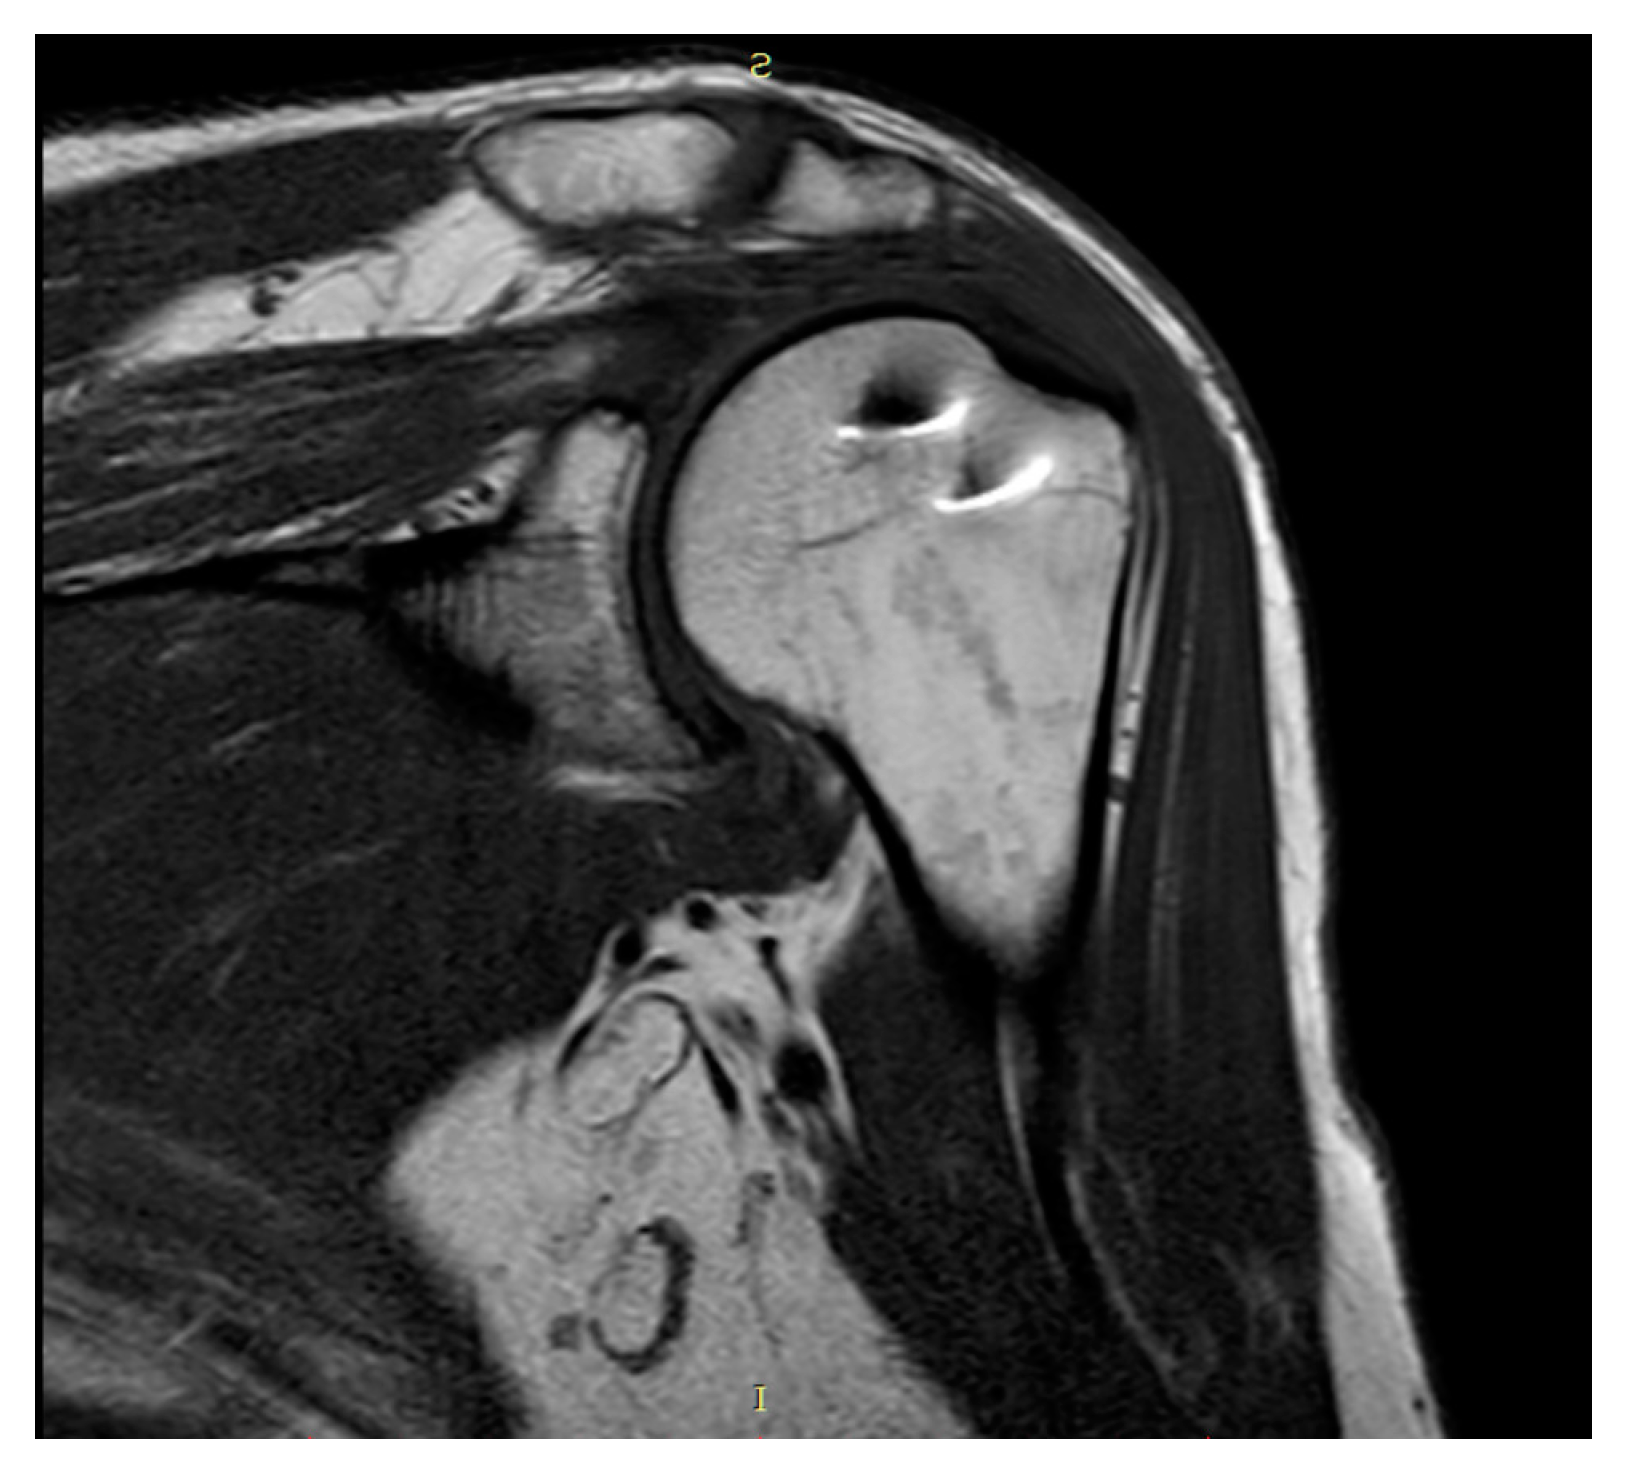

Plain radiographs and MRI showed coverage and centering of the humeral head, tendon continuity, and absence of fatty degeneration in all patients (Figure 3 and Figure 4).

Figure 3. Coronal T1-weighted MRI.